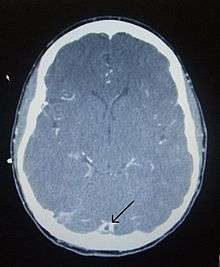

CT venogram showing a filling defect in the sagittal sinus (black arrow)

There are various neuroimaging investigations that may detect cerebral sinus thrombosis. Cerebral edema and venous infarction may be apparent on any modality, but for the detection of the thrombus itself, the most commonly used tests are computed tomography (CT) and magnetic resonance imaging (MRI), both using various types of radiocontrast to perform a venogram and visualise the veins around the brain.[1]

Computed tomography, with radiocontrast in the venous phase (CT venography or CTV), has a detection rate that in some regards exceeds that of MRI. The test involves injection into a vein (usually in the arm) of a radioopaque substance, and time is allowed for the bloodstream to carry it to the cerebral veins - at which point the scan is performed. It has a sensitivity of 75-100% (it detects 75-100% of all clots present), and a specificity of 81-100% (it would be incorrectly positive in 0-19%). In the first two weeks, the "empty delta sign" may be observed (in later stages, this sign may disappear).[5]